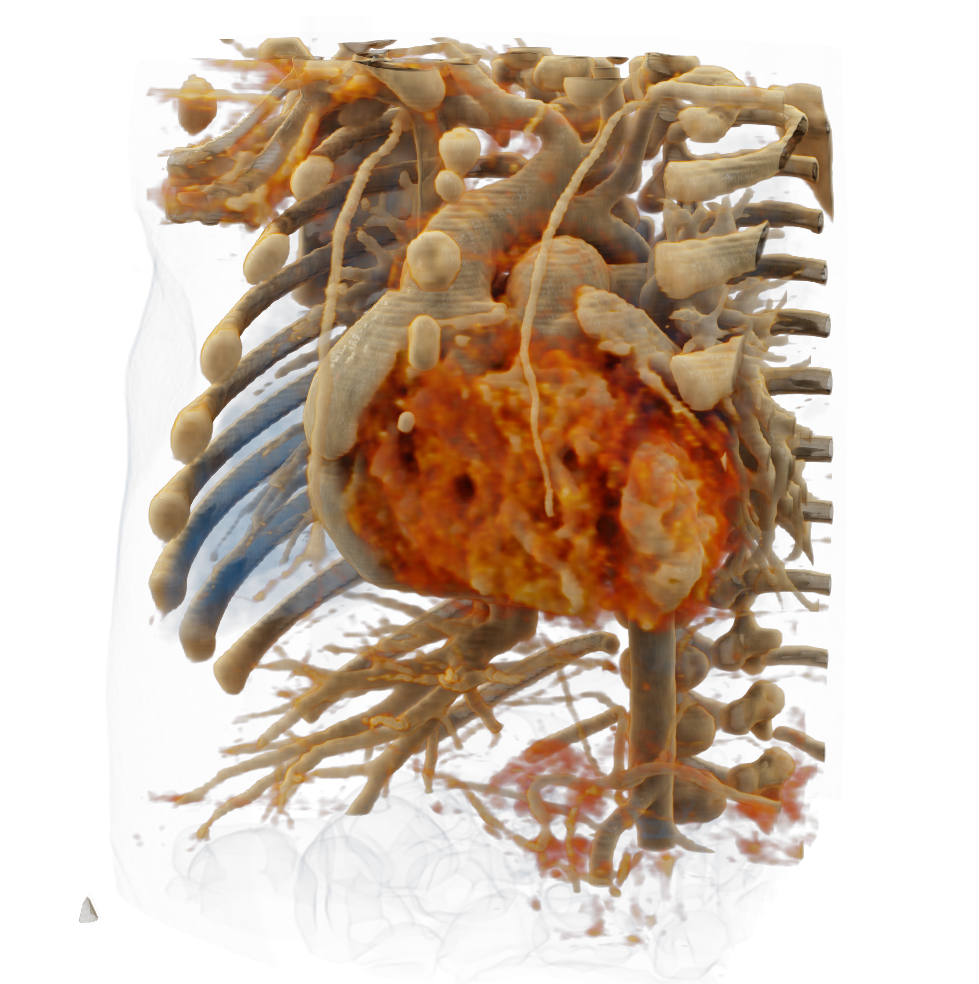

Visualize the smallest structures of the heart realistically without surgery? About the use of a prototype that makes this vision almost tangible.

Cardiac surgery is one of the most difficult procedures, and it gets even more complex when it comes to operating on tiny children’s hearts. Visualization techniques like cinematic rendering provide a detailed 3-D view of the patient’s heart and surrounding anatomy. But what happens when these images are turned into a hologram that can be rotated, zoomed, and looked at from all possible perspectives?